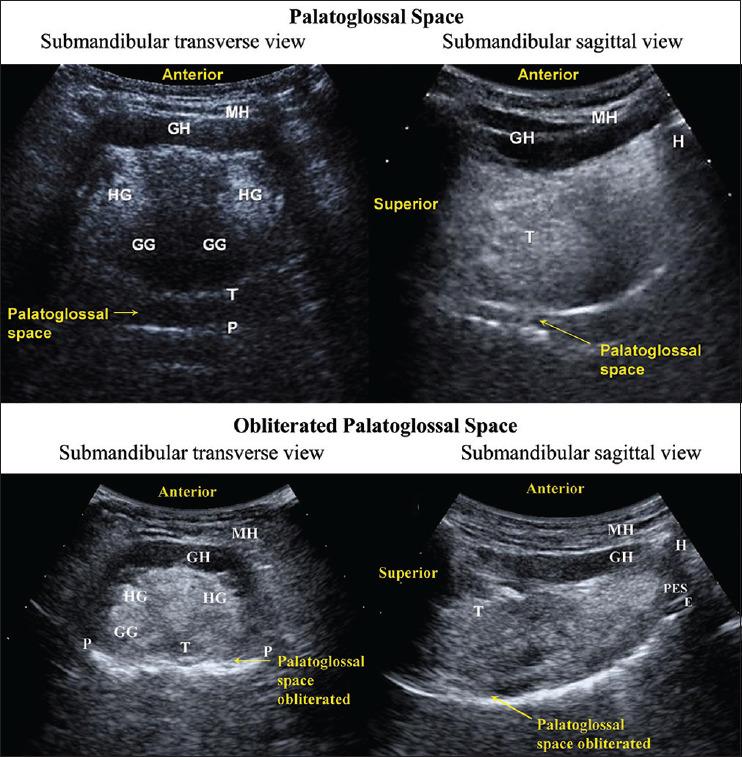

Ultrasonographic evaluation of palatoglossal space to predict difficult mask ventilation - A prospective observational study.

Indian J Anaesth. 2025 Mar;69(3):315-318. doi: 10.4103/ija.ija_963_24. Epub 2025 Feb 17.

DOI:10.4103/ija.ija_963_24

PMID:40161908

原文链接:https://pmc.ncbi.nlm.nih.gov/articles/PMC11952177/